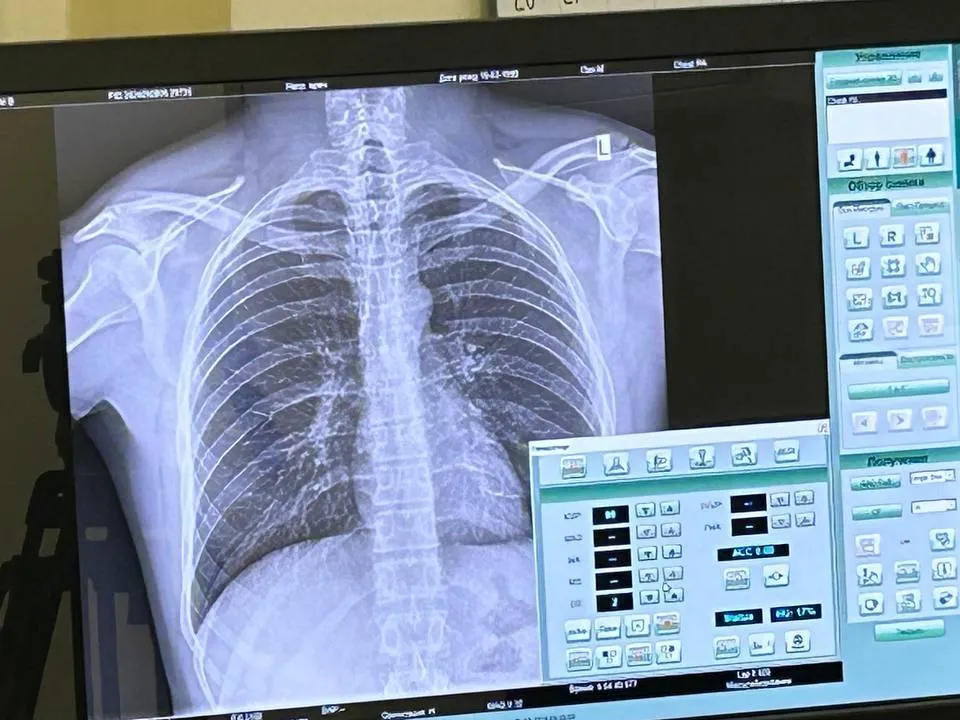

Патологии полости рта, образование щитовидной железы и кожи обнаружили у граждан, которые пришли проверить свое здоровье в Центре амбулаторной онкологической помощи Мытищинской больницы.

По данным Министерства здравоохранения Московской области, углубленное медицинское обследование прошли более ста пациентов, в том числе, приехавших в Мытищи из Пушкино и других городов. Все желающие могли без предварительной записи пройти комплексное обследование и получить консультацию врачей-онкологов, урологов, гинекологов и стоматологов. Подобные акции позволяют выявлять заболевания на ранней стадии, что является залогом успешного лечения.

Всего с начала года углубленное обследование в мытищинском центре прошли более 800 жителей региона. При этом, у 30 граждан выявили онкологию на ранней стадии заболевания.